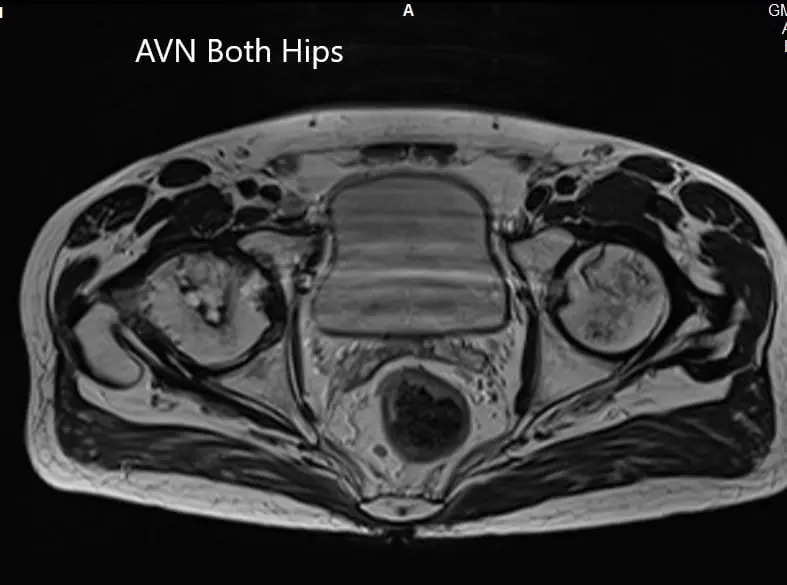

MRI suggested marked signal attenuation of bilateral femoral heads. There was a collapse of the right head and precollapse stage 2a of the left hip.

Axial section T1WI showing bilateral AVN of the femoral heads